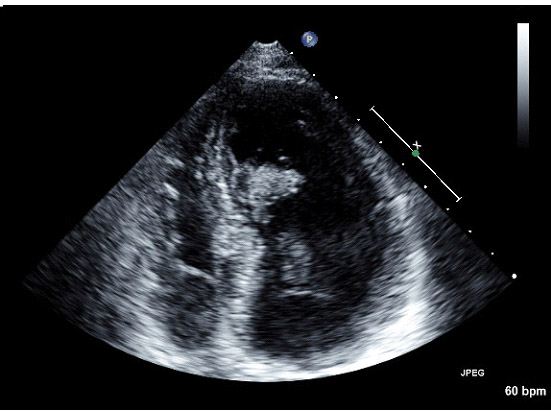

M/60 C.C. Atypical chest pain (since 2months) / Diabetes + / HR at MDCT scan: 70-75 bpm.

CHARY DURAIKANNU, VRR Diagnostics, INDIA

HIT : 82